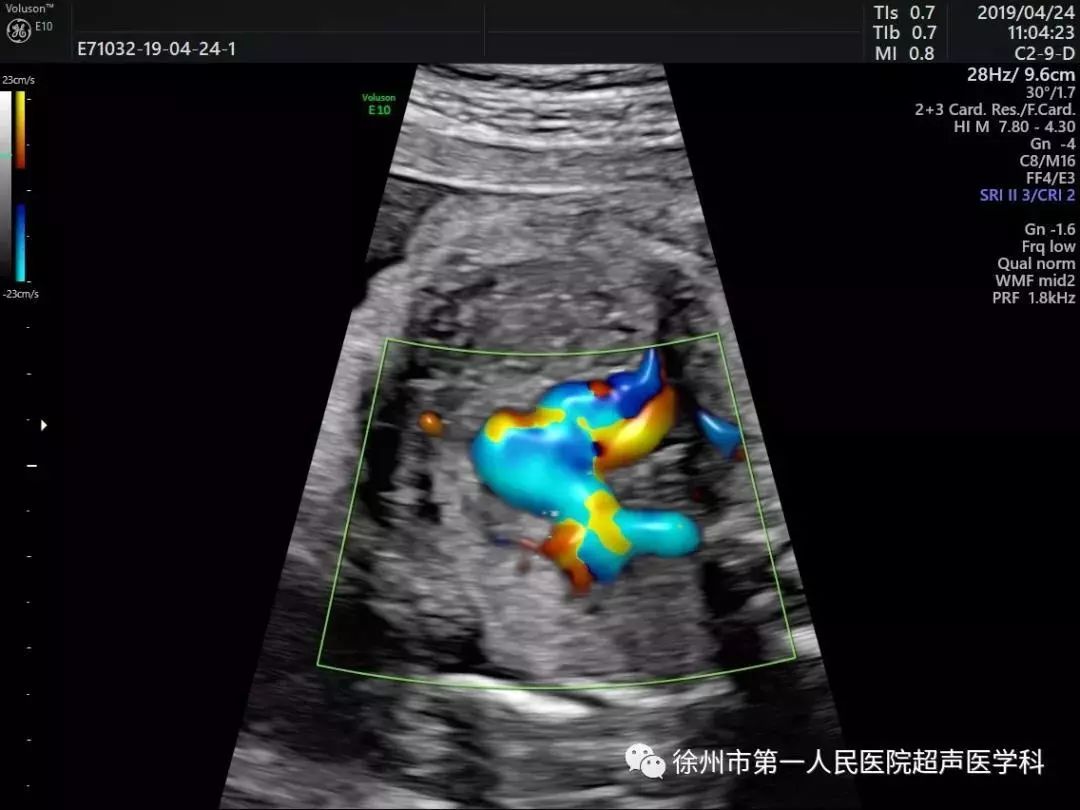

心脏超声检测对于超声图像质量及辅助的诊断工具要求非常高。美国GE Voluson E10优异的图像分辨率,能在四维空间内展现立体的心脏结构和功能,能更精准检查胎儿心脏发育情况。

E10具备一整套卓越的胎心成像技术(STIC),支持从胎儿心脏结构到心功能的分析,是胎儿心脏检测评估领域的技术领导。双平面成像技术可真实呈现胎心结构、脐带、血流变化,帮助临床医生及时作出确切诊断,是目前超声领域诊断的利器。